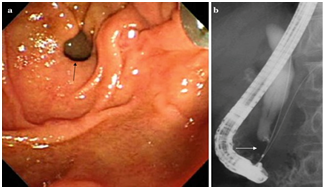

The etiology of acute cholangitis are summarized in Table 1. Choledocholithiasis used to be the most frequent cause, but recently the incidence of acute cholangitis caused by malignant disease, sclerosing cholangitis, and non-surgical instrumentation of the biliary tract has been increasing. It is reported that malignant disease accounts for about 1-30 % of cases with acute cholangiti17,18 (Figure 1-7).

Figure 1 Plastic stent migrated into common bile duct causing biliary obstruction.

Figure 7 Common bile duct stone.

Common bile duct stone (Figure 7)